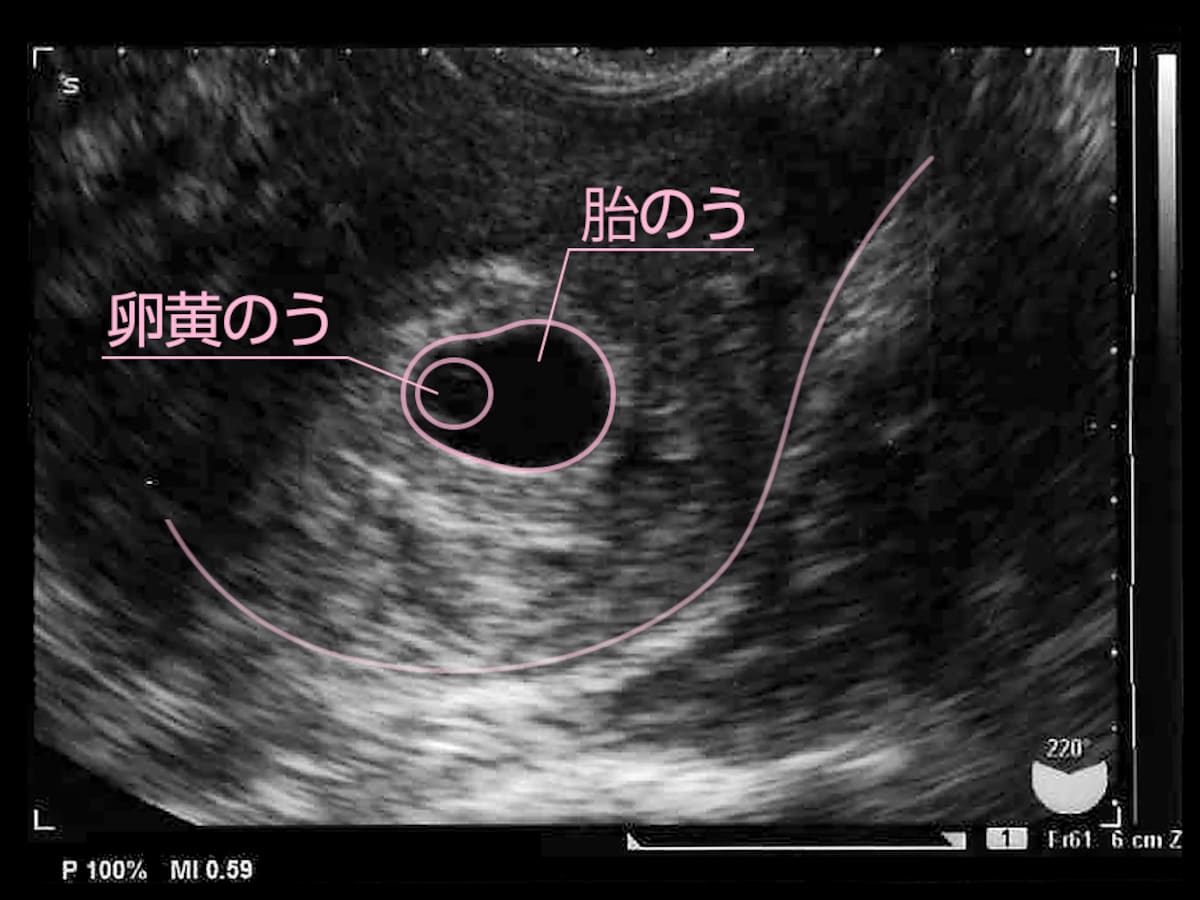

妊娠2ヶ月 妊娠4週 5週 6週 7週 妊娠初期 の超音波写真 妊娠 出産 育児に関する総合情報サイト ベビカム

胎嚢の大きさの平均ってどれくらいなの ママリ

妊娠2ヶ月 妊娠4週 5週 6週 7週 妊娠初期 のおなかの赤ちゃんの様子 妊娠 出産 育児に関する総合情報サイト ベビカム

妊娠2ヶ月 妊娠4週 5週 6週 7週 妊娠初期 の超音波写真 妊娠 出産 育児に関する総合情報サイト ベビカム